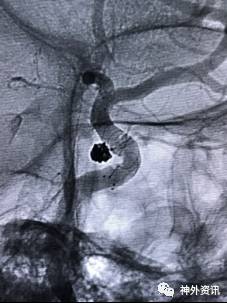

病例二

眼动脉动脉瘤,支架释放前,微导管成袢逆行到位